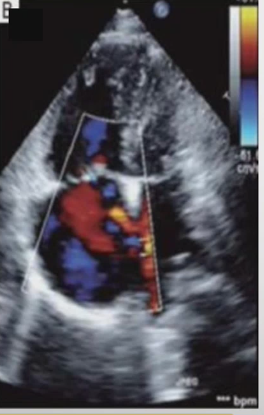

DX

Ostium secundum shunt

Left to Right shunt